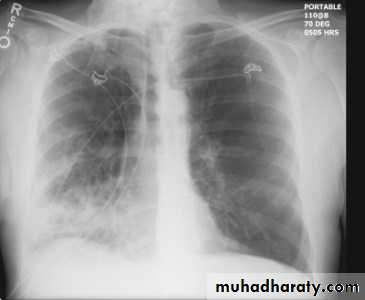

Chest imaging -2Pleural effusionPleural effusion tends to be used as a catch-all term denoting a collection of fluid within the pleural space. This can be further divided into exudates and transudates depending on the biochemical analysis of aspirated pleural fluid. Essentially it represents any pathological process which overwhelms the pleura's ability to reabsorb fluid.

Chest radiographs are the most commonly used examination to assess for presence of a pleural effusion, however it should be noted that on a routine erect chest x-ray as much as 250-600 ml of fluid is required before it becomes evident 6. A lateral decubitus film is most sensitive, able to identify even a small amount of fluid. At the other extreme, supine films can mask large quantities of fluid.

Both PA and AP erect films are insensitive to small amounts of fluid. Features include:

blunting of the costophrenic angle

blunting of the cardiophrenic angle

fluid within the horizontal or oblique fissures

eventually a meniscus will be seen, on frontal films seen laterally and gently sloping medially

A subpulmonic effusion (infrapulmonary effusion) may be seen when there is previously established pulmonary disease, but can also be encountered in normal lungs , They are more common on the right, and usually unilateral

with large volume effusions, mediastinal shift occurs away from the effusion (note: if coexistent collapse dominates then mediastinal shift may occur towards the effusion)